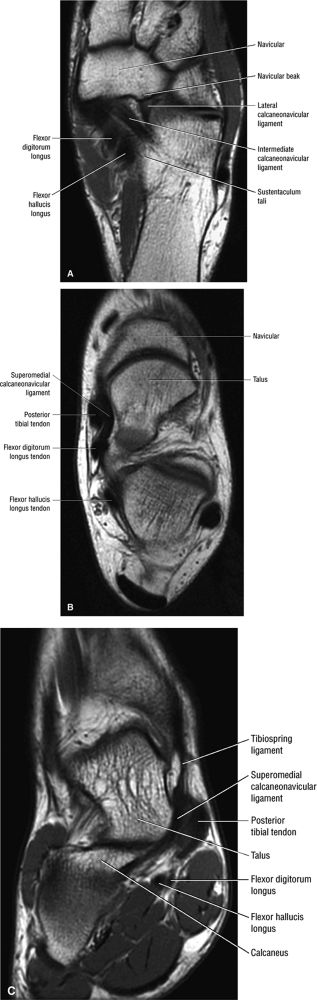

FIGURE 5.136 ● Spring ligament complex anatomy. Lateral-plantar oblique (A), plantar (B), and superior (C) views.